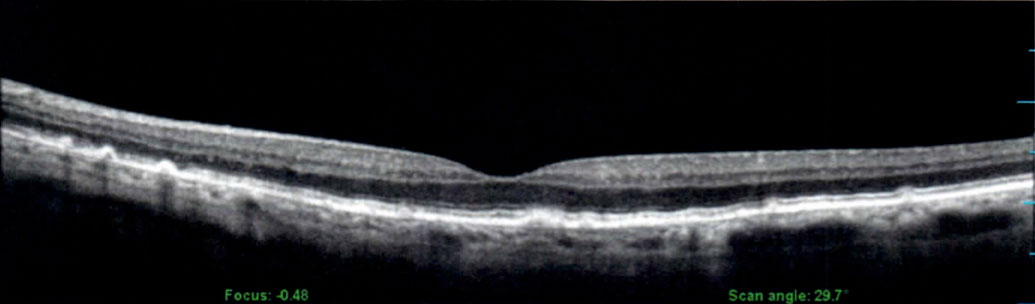

Optical Coherence Tomography

Optical coherence tomography (OCT) is an established medical imaging technique that uses light to capture three-dimensional images of the retinal structures.

Envision Eyecare offers this advanced technology to help with the diagnosis of several different types of retinal disorders.